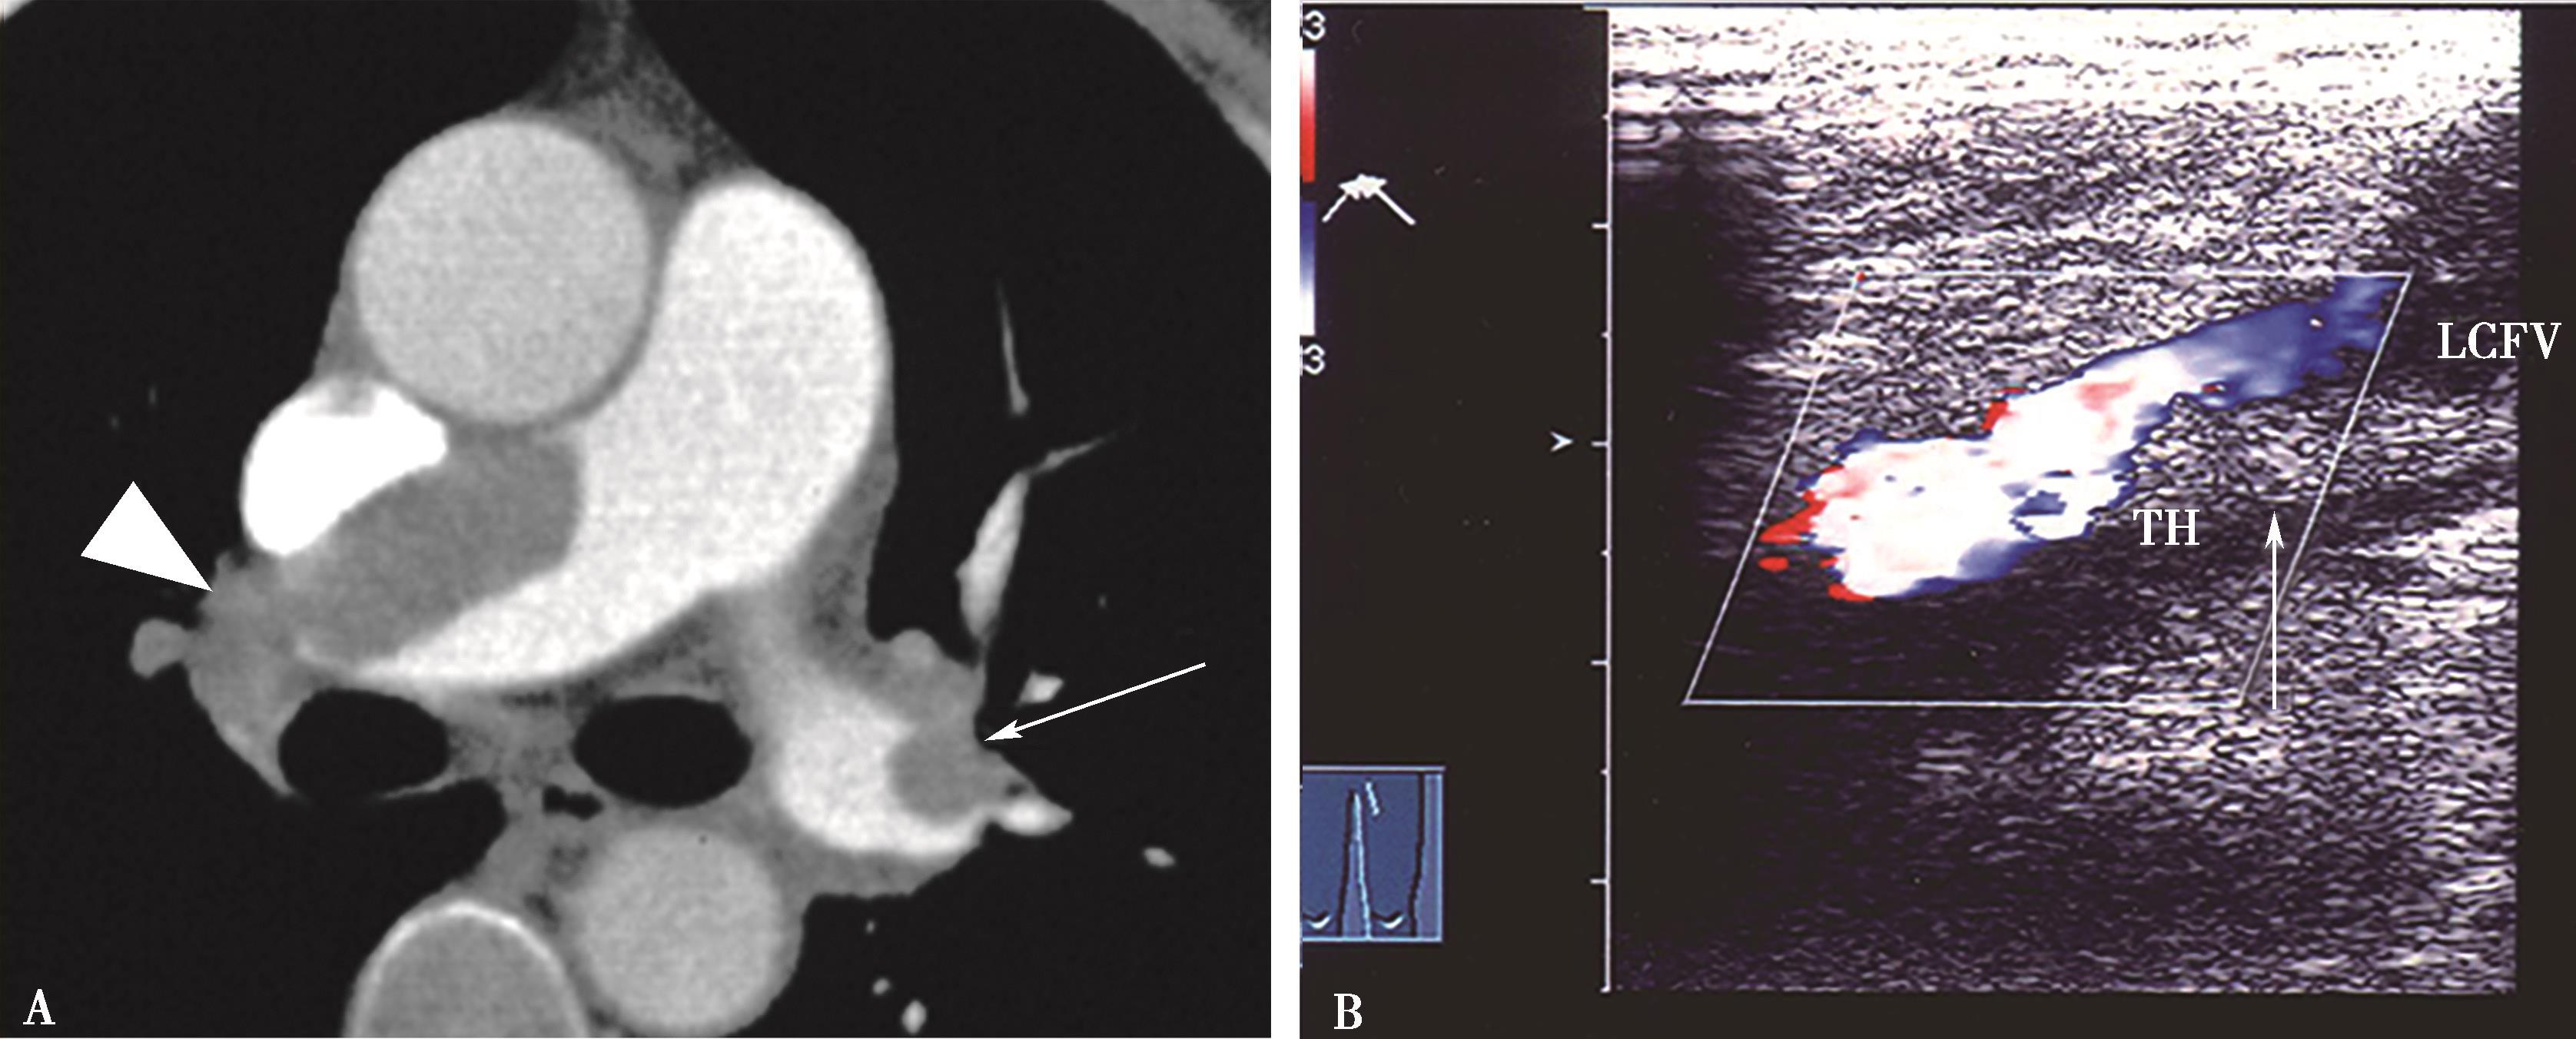

6.CT静脉造影(CTV)在CTPA检查中的必要性 CTPA检查可以一次性做下肢深静脉CT造影检查(CTV),方便患者,提高诊断敏感性。CTPA+CTV检出的敏感性提高为90%(单纯CTPA为 83%);而特异性 95%(单纯 CTPA为96%),两者相似。CTPA及CTPA+CTV两者对肺栓塞检出均有价值。但是CT检查有X线辐射。CTPA辐射剂量平均约为3mSv;而盆腔静脉CT扫描约6.0mSv;腿部约3.2mSv。因此,从防护考虑,CTPA不建议同时检查下肢深静脉检查。推荐下肢深静脉Doppler超声检查代替CTV。尤其对孕妇、儿童不推荐做CTV检查。临床实践证明CTPA阴性结果,下肢Doppler超声检查无下肢静脉血栓,患者除外PE,是可靠的。CTPA+下肢深静脉Doppler,是PE诊断检查最佳组合(图8-4-29)。

图8-4-29 急性肺栓塞,CTPA+Doppler超声下肢深静脉检查是最理想组合

A.横断像左右肺动脉大块充盈缺损(↑▲);B.下肢静脉Doppler超声检查,股静脉血栓栓塞(TH↑)